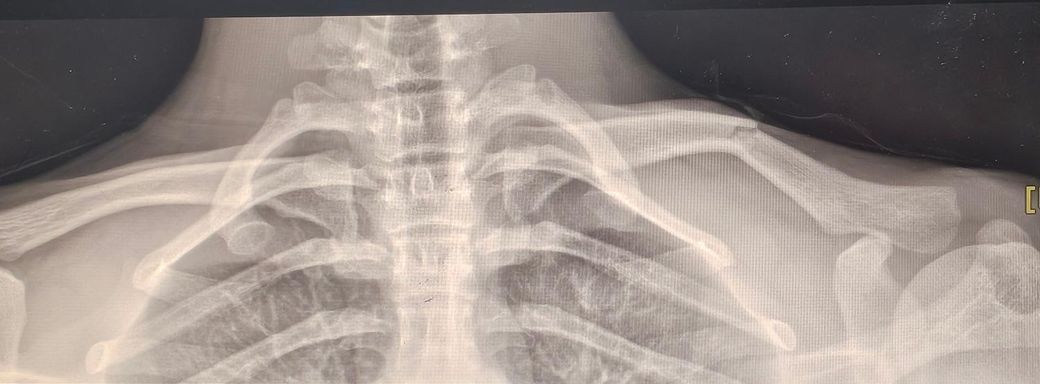

사진을 보았을 때, 단순히 금이 간게 아닌 뼈가 분리된 쇄골골절로 보여 이는 수술치료를 하는게 좋습니다.

엑스레이 한장만 가지고는 말씀드리기가 애매할 것 같습니다.

이것만 본다면 뼈의 어긋난 정도가 심하지 않아서 별다른 합병증이 없다면

수술을 하지 않고 뼈를 맞춘다음 고정을 해도 되지 않알까하는 생각이 듭니다

골절이 심하지 않고 편위가 크지 않다면 비수술적 치료법도 기대할 수 있으나 사진상으로는 절개 후 편위를 교정하고 고정술이 필요해보입니다. 핀제거는 모든 고정술에 필요한 것은 아니나 적응증이나 불편감이 큰 경우 다시 해당 부위 절개 후 핀을 수술적으로 제거합니다. 먼저 정형외과 담당의에게 정확한 수술 방법을 논의하시는 것이 좋겠습니다.

환자의 나이가 어리고, 환부 xray 소견을 볼 때 수술적 치료가 필요할 것으로 사료됩니다.

엑스레이 사진만으로는 평가하기 어려울 수 있으나 일단 엑스레이상 뼈가 심하게 어긋난 것으로 확인이 되고 수술적인 치료가 필요할 수도 있는 상태로 보입니다.